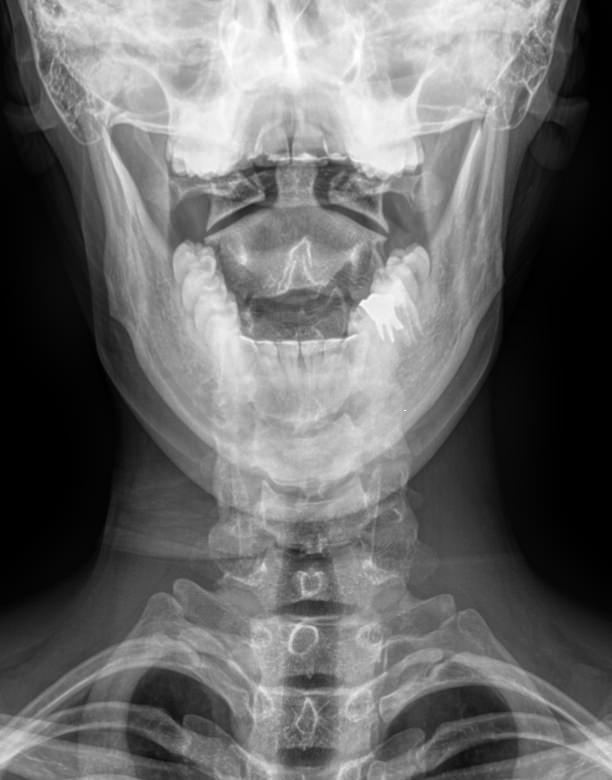

Рентгенография ― первое исследование, которое назначают при подозрении на патологию атланто-аксиального сочленения. На рентгеновском снимке хорошо видны костные образования и их изменения. Самое начало позвоночного столба лучше всего рассматривать в проекции «через открытый рот»: при такой укладке нижняя челюсть и затылочная кость не загораживают исследуемые элементы.

Что покажет рентген шейного отдела позвоночника через открытый рот

• Смещение позвонков друг относительно друга, на сколько и в какую сторону;

• Перелом, если он есть;

• Остеопороз тел позвонков;

• Симметричность и равномерность суставных щелей, костные разрастания;

• Равномерность межпозвоночных пространств.